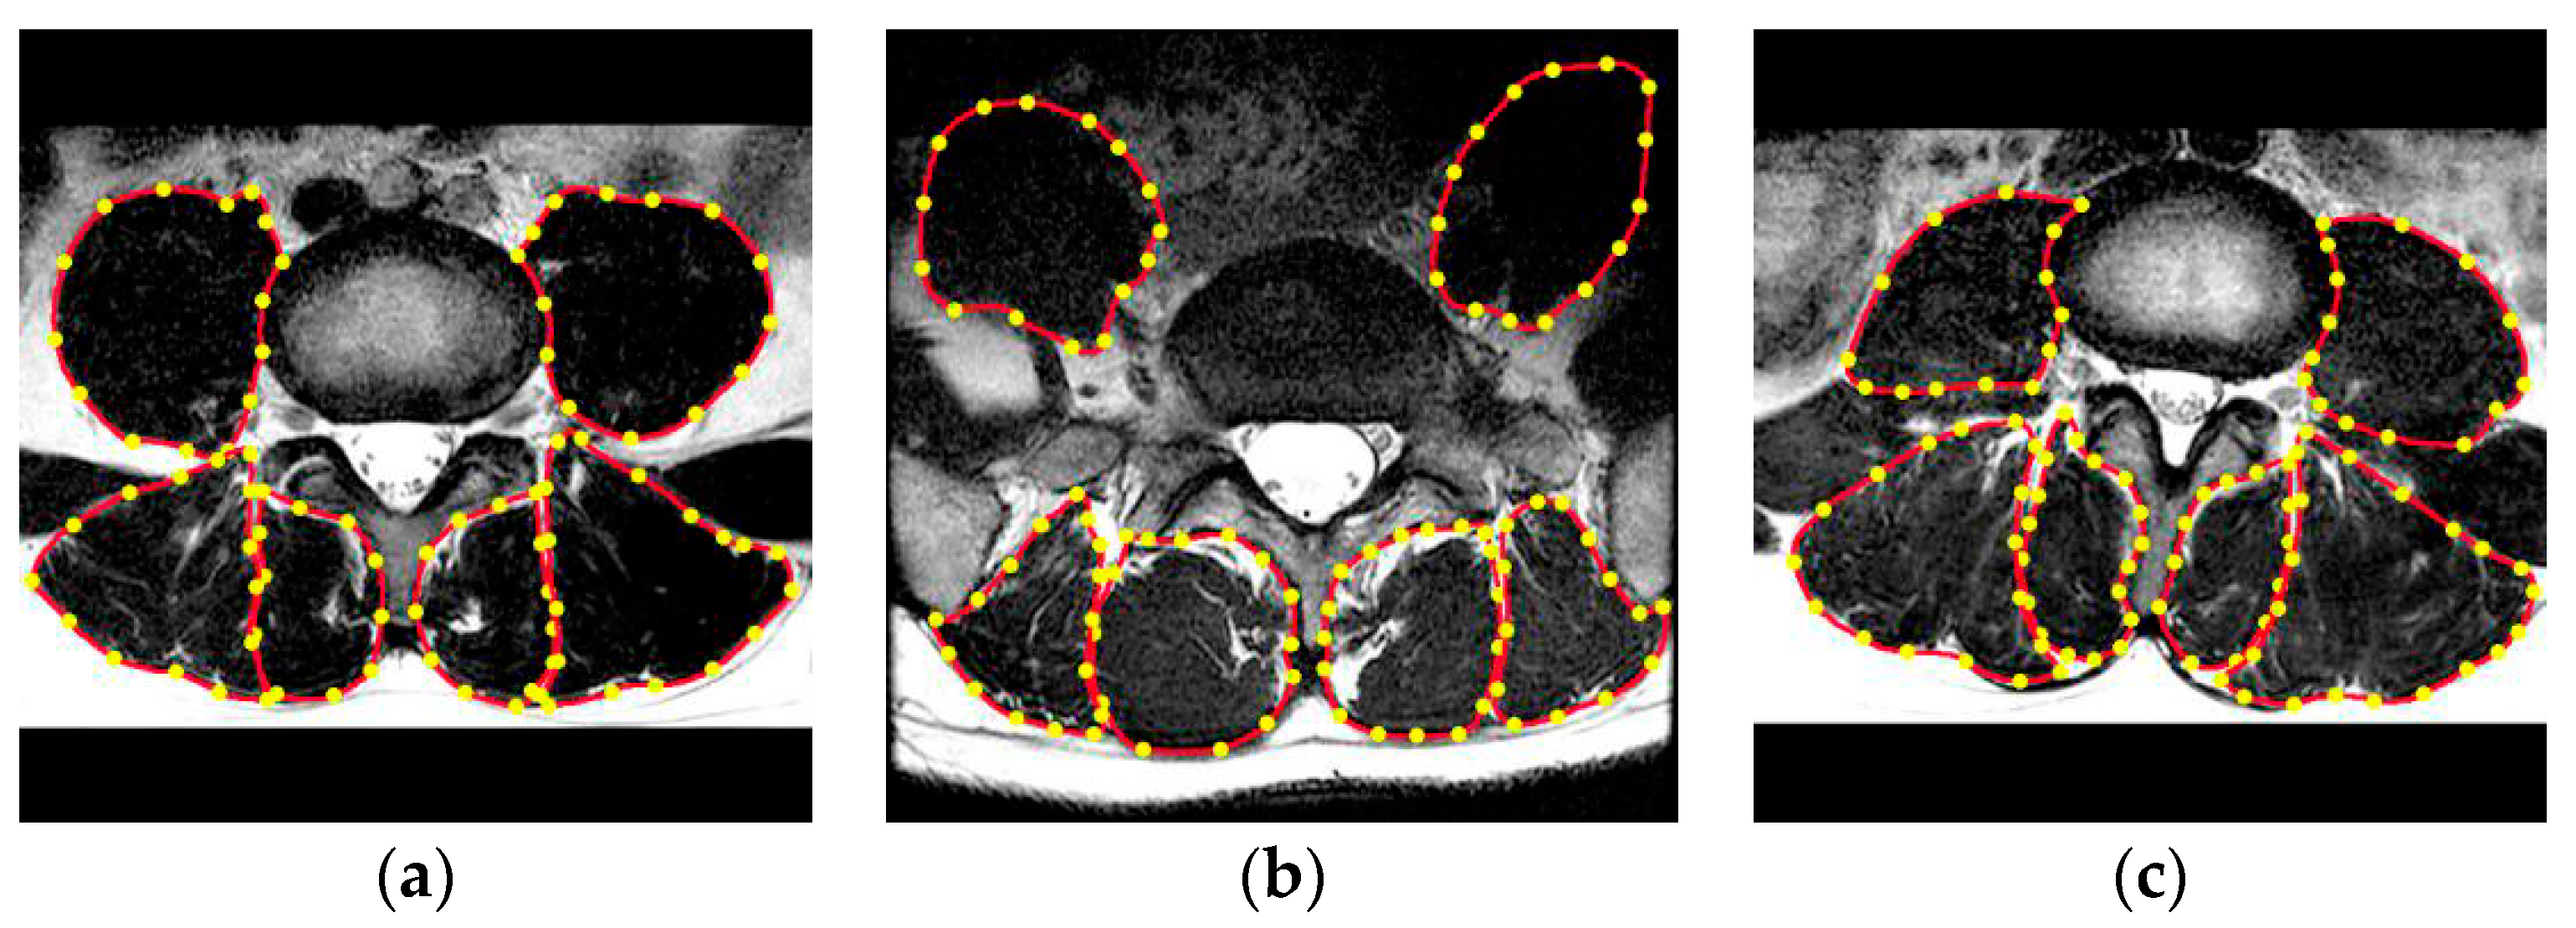

2.1. Preprocessing